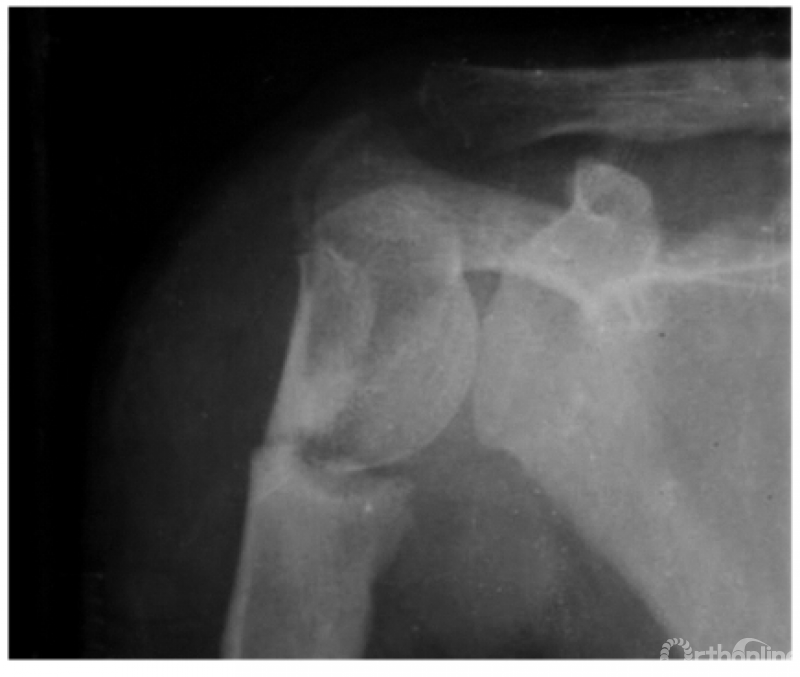

例1:肩关节外脱位并肱骨外科颈骨折,肱骨头上下倒置,远折端回缩至关节盂处致形成假关节(如下图)。